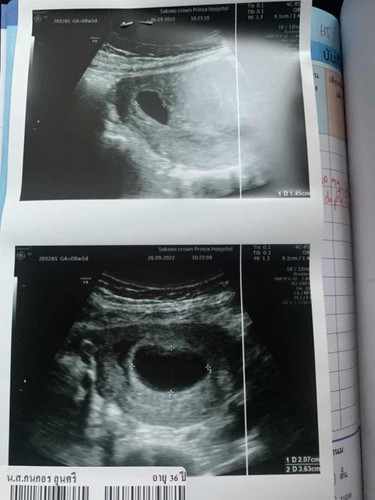

แม่ๆบ้านไหน ซาวด์เจอตัวอ่อนกี่วีคกันบ้างคะ บ้านนี้ 8 วีค ซาวด์ไม่เจอตัวอ่อนเลยค่ะ คุณหมอบอกว่าอาจท้องลม😔😔😔 เครียดมากเลยค่ะ

8 w. ต้องเห็นตัวน้องแล้วนะคะ เราเคยท้องลมค่ะซาวด์ตอน 6w ไม่เจอตัวอ่อน(แพ้ท้องอยู่ค่ะ) นัดอีก3สัปดาห์ (ระหว่างรอนัดถัดไปจู่ๆอาการแพ้ท้องหายไป) ถึงวันนัด9wถุงตั้งครรภ์ใหญ่ขึ้นแต่ก็ยังไม่เจอซาวด์หน้าท้องและช่องคลอด คอนเฟริ์ม70%ที่จะท้องลมแต่ไม่มีเลือดออก หมอเลยให้โอกาสอีก 2 อาทิตย์มาใหม่ ผ่านไป5วัน มีเลือดออกมาหาหมอใหม่ ก็ยังไม่เจออีกคอนเฟิร์ม100%ท้องลม นัดขูดมดลูกเลย ถ้ายังไม่มีเลือดออกอย่าพึ่งกังวลเลยค่ะ น้องอาจจะโตช้า ช่วงนี้ก็กินยาบำรุงไปก่อนแต่ก็อยากให้ทำใจไว้สักนิดนึงนะคะ จากที่ดูใบซาวด์ถุงตั้งครรภ์โตมากแล้ว มีสิทธิ์จะท้องลมมากค่ะ น้องอาจจะยังไม่พร้อม ไว้บำรุงเริ่มใหม่ติดง่ายกว่าเดิมค่ะ ตอนนี้เราก็ท้องใหม่แล้ว22wแล้วค่ะ เป็นกำลังใจให้นะคะ✌🏻❤️